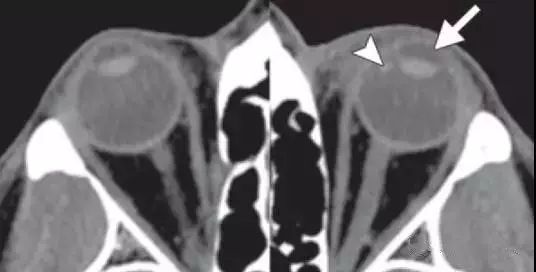

创伤性白内障

对眼球的钝性创伤也可能破坏晶状体囊 , 进而导致晶状体水肿并最终导致白内障的形成 。 白内障在临床检查时比较容易诊断 。

在CT上 , 与未受影响的晶状体相比较 , 受影响的水肿的晶状体可能表现为相对低密度 。 成熟的白内障可能表现为高密度影或含钙化